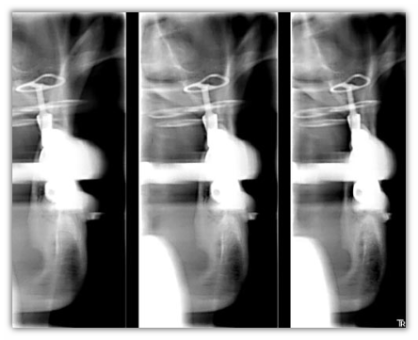

Il sistema KODAK 8000 offre le seguenti opzioni di imaging:

• Articolazione temporomandibolare (2 o 4 viste)

• Panoramica

• Panoramica segmentata

• Seno mascellare

Espandete le funzionalità diagnostiche del vostro sistema KODAK 8000 con l'opzione cefalometrica digitale.